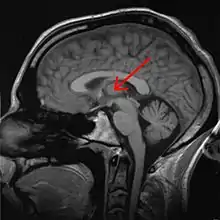

Tálamo (anatomia)

O tálamo é uma estrutura localizada no diencéfalo, entre o córtex cerebral e o mesencéfalo, formada fundamentalmente por substância cinzenta (núcleos de neurônios) do encéfalo [1]. São duas massas neuronais situadas na profundidade dos hemisférios cerebrais. Dentre suas funções estão a transmissão de sinais motores e sensitivos para o córtex [2], além da regulação da consciência, sono e estado de alerta.

O tálamo é um conjunto bem definido de vários núcleos de neurônios e forma uma parte maior do diencéfalo. Existem dois deles situados em posições simétricas, à esquerda e à direita, cada um covixem cerca de 1 cm de comprimento. Sua extremidade anterior é estreita e arredondada, e constitui a parede posterior do forame interventricular; a porção posterior é expandida e está acima do colículo superior; a superfície inferior situa-se continuamente ao tegmento do mesencéfalo; sua face medial está confrontada com a mesma do outro tálamo e contém uma região de comunicação com ele, a adesão intertalâmica, que está rodeada pelo terceiro ventrículo.